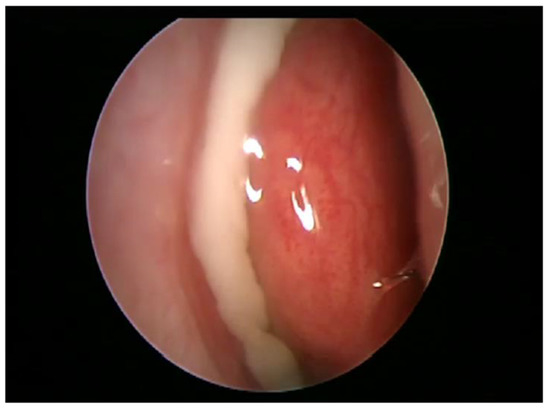

3. Presentation